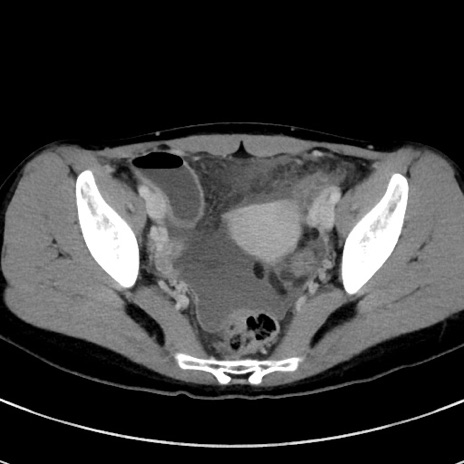

症例17(横断像)

【症例】20歳代女性

【主訴】嘔吐、下腹部痛

【現病歴】昨日夕食後に嘔吐し下腹部痛が出現。本日になっても嘔吐持続し改善しないため来院。

【身体所見】意識清明、BT 37.2℃、BP 108/67mmHg、腹部:平坦、やや硬、下腹部正中から右にかけて圧痛あり、反跳痛軽度あり、tapping pain(+)。

【データ】WBC 13600、CRP 14.94